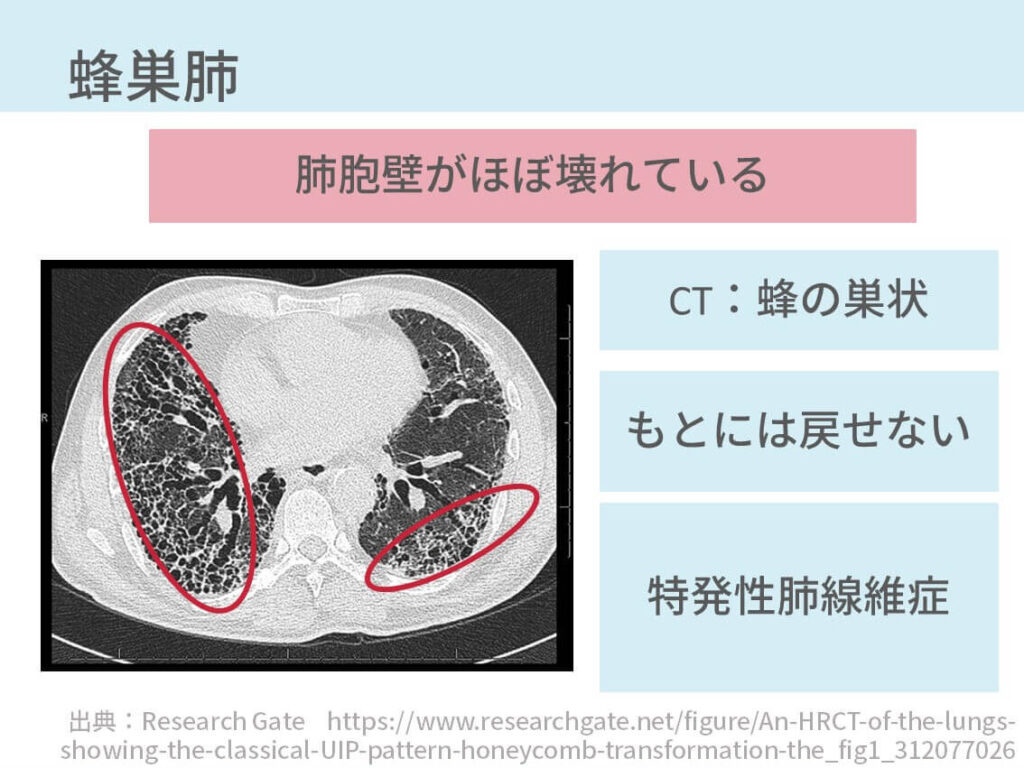

間質性肺炎の胸部CTの所見【悲報:胸部CTからは診断できません,

間質性肺炎の胸部CTの所見【悲報:胸部CTからは診断できません, 胸部X線読影道場ふたたび630: やさしイイ呼吸器教室,

胸部X線読影道場ふたたび630: やさしイイ呼吸器教室, 軸位断の肺、縦隔、心臓の解剖 | e-Anatomy,

軸位断の肺、縦隔、心臓の解剖 | e-Anatomy, 胸部CT道場36・飛び飛びに白くなる陰影32・結節影・腫瘤影3,

胸部CT道場36・飛び飛びに白くなる陰影32・結節影・腫瘤影3, 胸部X線・CTの読み方やさしくやさしく教えます!改訂版 - 羊土社「胸部のCT」村田 喜代史 / 上甲 剛 / 村山 貞之定価: ¥ 15000#村田喜代史 #村田_喜代史 #上甲剛 #上甲_剛 #村山貞之 #村山_貞之 #本 #自然/医療・薬学・健康書き込み等はありません。やさしい皮弁。申し訳ありませんが値下げはできませんので予めご了承ください。心臓血管外科手術 虎の巻 *裁断済み。(まとめ買いいただく場合には値下げを検討させていただきます。衛生化学詳解 上 第3版 京都廣川書店。)